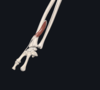

name the vessels in the image

top arrow= radial artery

bottom arrow= ulnar artery